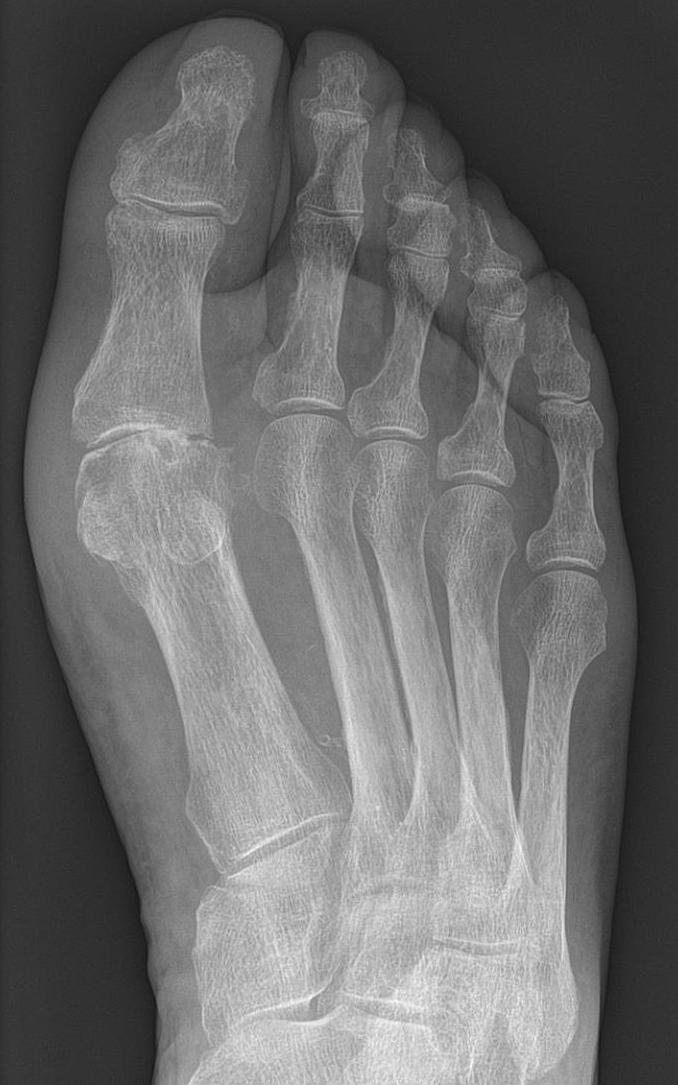

Saturnine gout can affect any joint in your body. But mostly lower extremity joints are affected the most. This includes knees, ankles, and toes. The symptoms of Saturnine gout are almost the same as other types of gout. The symptoms may include: